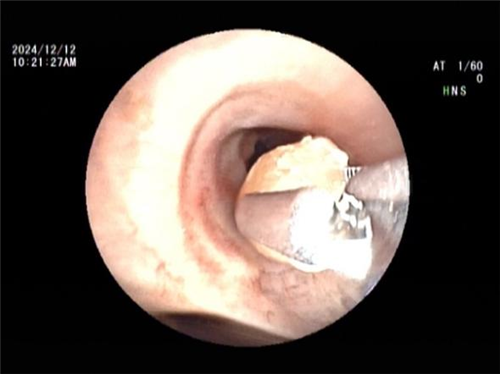

王海龙主任迅速组织团队对孟某展开全面综合评估,结合患者症状及各项检查结果,高度怀疑其患有吸入性气管异物并由此引发阻塞性肺炎。在与孟某及其家属进行充分且细致的沟通交流后,王海龙主任决定亲自为患者实施电子支气管镜检查。在支气管镜深入探查过程中,清晰可见患者右中叶支气管被一异物牢牢阻塞管腔。此异物表面光滑,质地极为脆弱,不仅易碎,还容易软化变形,这一系列棘手问题使得异物取出难度呈指数级增加。手术过程中,任何细微的失误都可能导致异物掉落至气管深部,从而引发更为严重且复杂的后果。但王海龙主任凭借其精湛高超的医术与沉稳冷静的临场应变能力,运用异物钳小心翼翼地进行操作,经过多次精准尝试,最终成功取出一枚长径约 1cm 的异物。术后,孟某的呼吸即刻恢复通畅,经过 5 天系统且精心的治疗,咳嗽、咳痰症状显著缓解,胸闷、气促等不适症状全然消失,肺部感染病灶也得到明显吸收。经确认,此次引发孟某一系列病痛的 “罪魁祸首” 竟是一粒花生米。